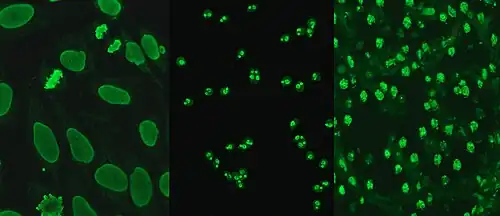

HEp-2

Hep-2 cells, originally of laryngeal carcinoma origin, are actually a contamination of HeLa cells.[26] They are routinely used in the diagnosis of ANA in diagnostic laboratories. HEp-2 cells provide a greater ability to differentiate patterns of ANA than animal sections, due to the large nuclei and high mitotic rate of the cell line. Upon incubation with serum containing anti-dsDNA antibodies and fluorescent labelled secondary antibodies, homogeneous staining of interphase nuclei and condensed chromosomal staining of mitotic cells can be seen.[27]